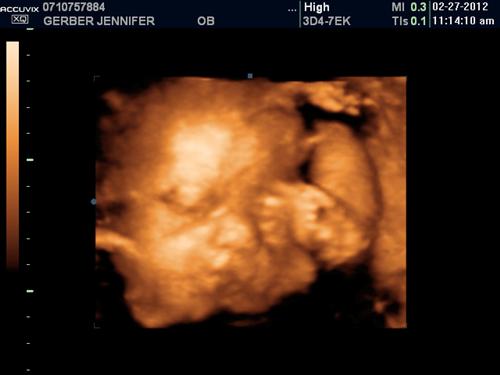

baby!